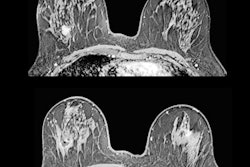

Contrast-enhanced mammography exam of both breasts in two views. In the first two low-energy images (A, B), an ill-defined mass can be seen in the upper outer quadrant of the right breast at the location of a palpable mass in a 52-year-old patient. In the left breast, no relevant abnormalities can be detected. In the recombined images (C, D) of a contrast-enhanced mammography examination, contrast uptake can be appreciated. The recombined images show an irregular enhancing mass in both breasts -- both in the upper outer quadrant. Tissue sampling revealed a bilateral invasive breast cancer of no special type. A breast MRI examination performed prior to surgery also confirmed the presence of two irregular enhancing masses on these contrast-enhanced T1 weighted images (E: top example is the cancer in the right breast; bottom example is the left breast). All images courtesy of Dr. Marc Lobbes, PhD.